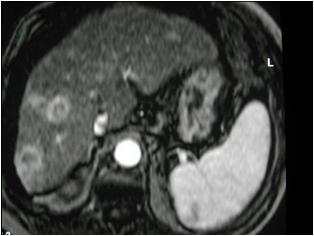

Following gadolinium administration